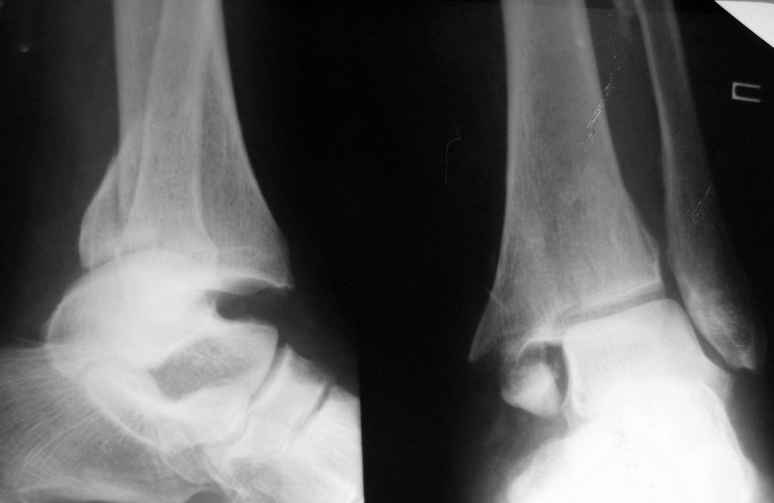

31 августа 2007 года была оперирована в другой области по поводу DS Закрытого двухлодыжечного перелома правой голени с подвывихом стопы кнаружи , кзади. Разрыв дистального межберцового синдесмоза. Перелом заднего края большеберцовой кости справа. Поступила в наше отделение со швами ,с некрозом медиальной поверхности правого голеностопного сустава. Проведено : снятие швов , антибиотики , некрэктомия с последующей кожной пластикой .Заживление 20 декабря 2007 года ,выписана из стационара . 3 марта 2008 года поступает с гиперемией , отек , флюктуацией. В настоящее время имеется рана по медиальной поверхности правой голени ,отеки и гиперемия сохраняется .Наша тактика:1) снятия воспалительного процесса, 2) удаление металлоконструкции, 3) выполнения артродеза правого голеностопного сустава.

Если можно, более полную информацию. Rg. Очень интересно местный статус, если можно фото....

Несросшийся перелом внутренней лодыжки и даже ложный сустав там же ,обычно, не может быть серьезной проблемой для пациента, при условии сохранности дистального синдесмоза. Но остеомиелит? и нет ли там остеоартрита голеностопного сустава? Если там имеется свищ, то попробуйте ввести в него контраст (прим. - урографин) и выполнить Rg в 2х пр. Жду дополнительную информацию. С уважением.

Алексей20 15 Март 2008, 14:03

Не очень удачный вариант остеосинтеза: сохранен подвывих стопы, синдесмоз не достаточно репонирован. Думаю, в данном случае у пациента д-з: остеоартрит правого голеностопного сустава, послеоперационный остеомиелит правой голени. Предлагаю тактику: одномоментно выполнить удаление металлоконструкции, хирургическую обработку очага остеомиелита, резекцию голеностопного сустава, артродез аппаратом. Другие методы лечения не привидут к купированию гнойного процесса. Так как полость сустава в настоящее время имеет вид пиогенной капсулы, в которой будет поддерживаться гнойный процесс даже после заживления свища, с последующим его открытием и опорожнением гноя.